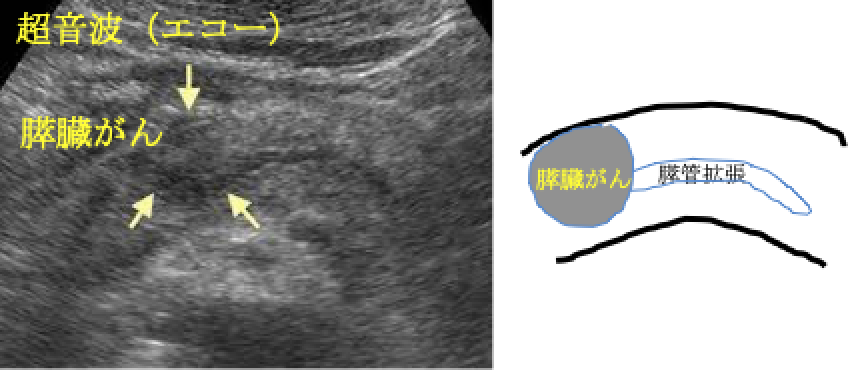

② 腹部超音波(エコー)

膵臓がん・膵管拡張・膵のう胞をみつけます。体型やガスでみえないこともあります。

膵臓がんはすい管(消化液〈=すい液〉の通り道)から発生する膵管がんと言われています。 膵臓がんを発症すると、すい管が狭くなり、膵液が停滞します。その際に、主膵管拡張・膵のう胞(分枝膵管拡張)・脂肪変性(膵臓の凹みや痩せ)・腫れといった変化を引き起こします(膵臓がんの間接所見)。これにともなって、膵臓の炎症を起こしたり(みぞおちの痛み)、膵臓のはたらきが低下します(糖尿病の発症や悪化、味覚の変化、下痢など)。顕微鏡レベルの膵臓がん(上皮内がん)でも上記の間接所見や症状を伴うものがあることがわかってきました。膵臓がんが発生してから転移するまで約7年かかると言われております。この間に膵臓の形や膵管の変化をとらえることで早期の膵癌が発見できる可能性があります。